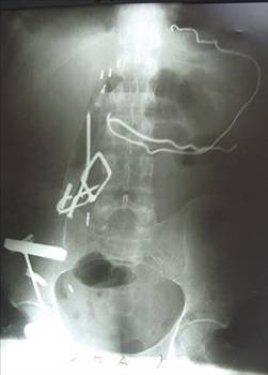

3. Kazakistan'da 7 yaşındaki bir erkek çocuğun karnında ikizi bulundu.

Kazakistan'da 7 yaşındaki bir erkek çocuğun karnında ikizi bulundu.

4. Simkent şehrinde yaşayan çocuğun karnındaki şişliği fark eden okul doktorunun hastaneye başvurması sonucunda hemen ameliyata alınan çocuğun karnından saçları ve tırnakları uzamış bir cenin çıkarıldı.

Simkent şehrinde yaşayan çocuğun karnındaki şişliği fark eden okul doktorunun hastaneye başvurması sonucunda hemen ameliyata alınan çocuğun karnından saçları ve tırnakları uzamış bir cenin çıkarıldı.

5. İran'da, korkusunu bastırmak ve sıkıntılarından kurtulmak için madeni nesneleri yiyen genç kızın karnından ameliyatla yarım kilogram ağırlığında metal parçalar çıkarıldı.

İran'da, korkusunu bastırmak ve sıkıntılarından kurtulmak için madeni nesneleri yiyen genç kızın karnından ameliyatla yarım kilogram ağırlığında metal parçalar çıkarıldı.

6. 17 yaşındaki genç kızın karnından çıkarılan madeni nesnelerin arasında jilet ve çiviler de bulundu.

17 yaşındaki genç kızın karnından çıkarılan madeni nesnelerin arasında jilet ve çiviler de bulundu.